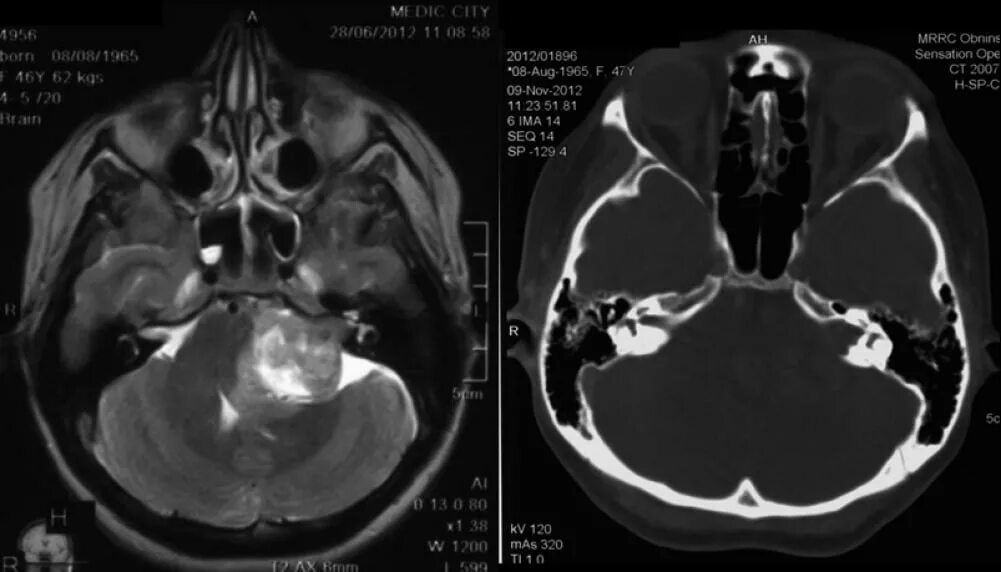

Мрт головного мозга мосто мозжечкового угла